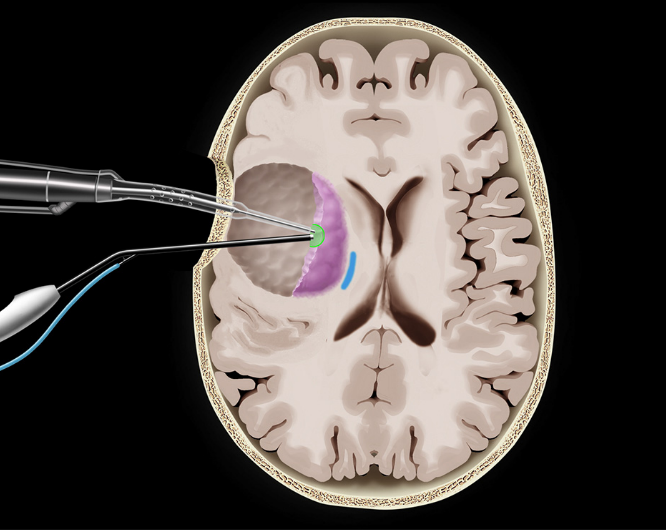

唤醒手术最大安全切除左中央区胶质瘤,术中照片:皮层电刺激(2.5mA)定位出患者感觉区感觉区皮质(标志点1小指,2拇指,3口角)和口角运动区(标志点4)以及数数中断并出现口角抽搐癫痫发作(标志点5),其中标志点5在肿瘤表面,肿瘤位于左中央前回腹侧。

保留功能区,尤其是标志点5,显微镜下电凝周边蛛网膜,切开至皮层下,在保留患者功能区的前提下,在持续监测患者运动和命名的前提下,先分离前方,至正常蛛网膜,再分离后方至正常蛛网膜。

电刺激为食指感觉(标志点9),下方切除标志点5下方的肿瘤,病人无明显失语,将标志点5切除,上方达一层蛛网膜,电刺激为手动(标志点7),深部切除过程病人语言含糊,电刺激为口角运动(标志点8)。

• 显微手术:蛛网膜下操作保留重要血管(动脉-静脉)、先切除关键部位。

• 按照功能边界最大程度切除肿瘤。